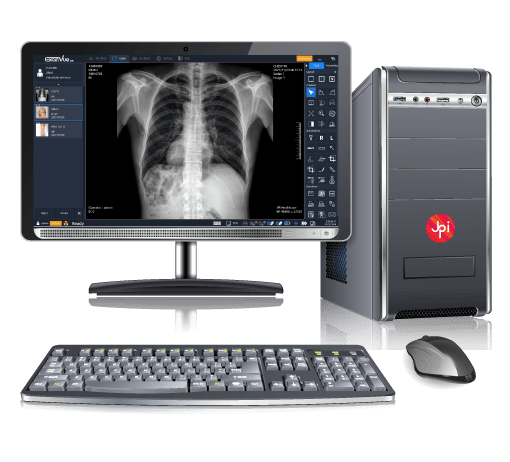

PACS DE EXAMVUE

EXAMVUE DUO ACQUISITION SOFTWARE

Diseñado para optimizar la captura de imágenes radiográficas con la más alta calidad y eficiencia

Acceso Seguro y Rápido a tus Imágenes Médicas

En LinkMedic llevamos la radiología al siguiente nivel con nuestro sistema PACS en la nube. Procesa, comparte y almacena radiografías digitales de forma eficiente y sin límites geográficos. Garantizamos acceso seguro, imágenes de alta calidad y una experiencia ágil que optimiza tu flujo de trabajo, mejorando la atención de tus pacientes en cualquier momento y lugar.